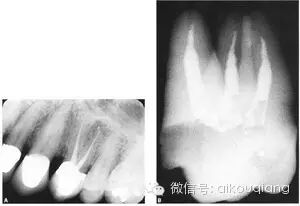

“G型扩孔钻预备:应用GG钻预备根管冠2/3可获得良好的根管冠部通道。GG钻进人根管前,一定要用10#或l5#根管锉探查和通畅根管,如果GG钻1#进入根管有困难时,应初步预备根管,再使用GG钻进入。一般来说,GGl#进入根管l6~17mm;GG2#,GG3#后退2~3mm;GG4#进入根管口下2~3mm;GG5#,GG6#仅作根管口以上部分预备,便于髓腔与根管口形成直线通道。GG钻勿进入根管的深部,避免过度去除牙本质,造成根管壁的薄弱,形成穿孔或瓶颈样预备(见下图)

口腔H锉怎么消毒根管治疗器械的选择_https://www.jmylbn.com_新闻资讯_第21张

图 根管带状侧穿(stripping,lateral wall perforation)

口腔H锉怎么消毒根管治疗器械的选择_https://www.jmylbn.com_新闻资讯_第22张

图 根管的瓶颈样预备(右图)